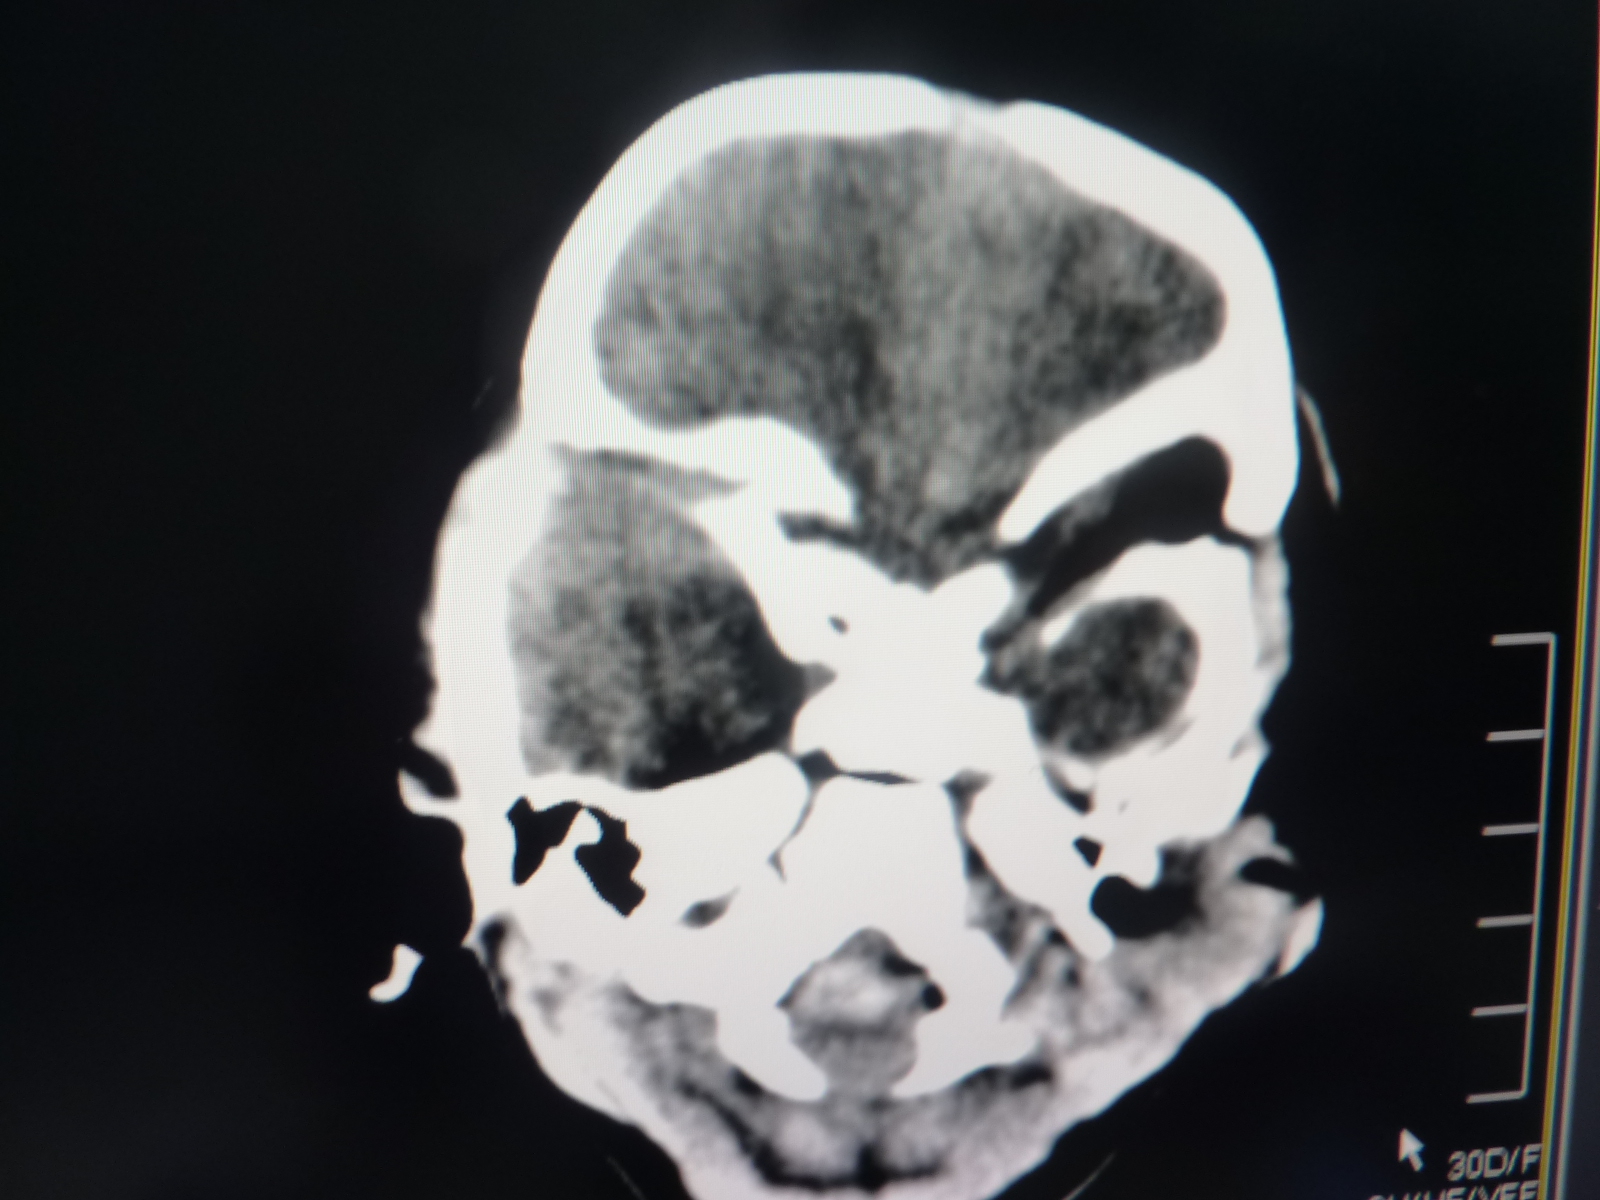

抽搐,脑积水,血管畸形并出血,请问是哪个部位畸形?脑室内?还是颞叶?

近右侧侧脑室三角区内可见弯曲条带状斑片状高密度影,高密度周围见片状低密度影。三脑室、侧脑室显著扩张。考虑:右侧侧脑室后角区脑血管畸形并出血伴梗阻性脑积水。

右侧脑室出血并交通性脑积水【四脑室不大 考虑血块阻塞中脑导水管】

侧脑室内血管畸形伴出血可能。

应排除右侧侧脑室三角区肿瘤出血的可能!